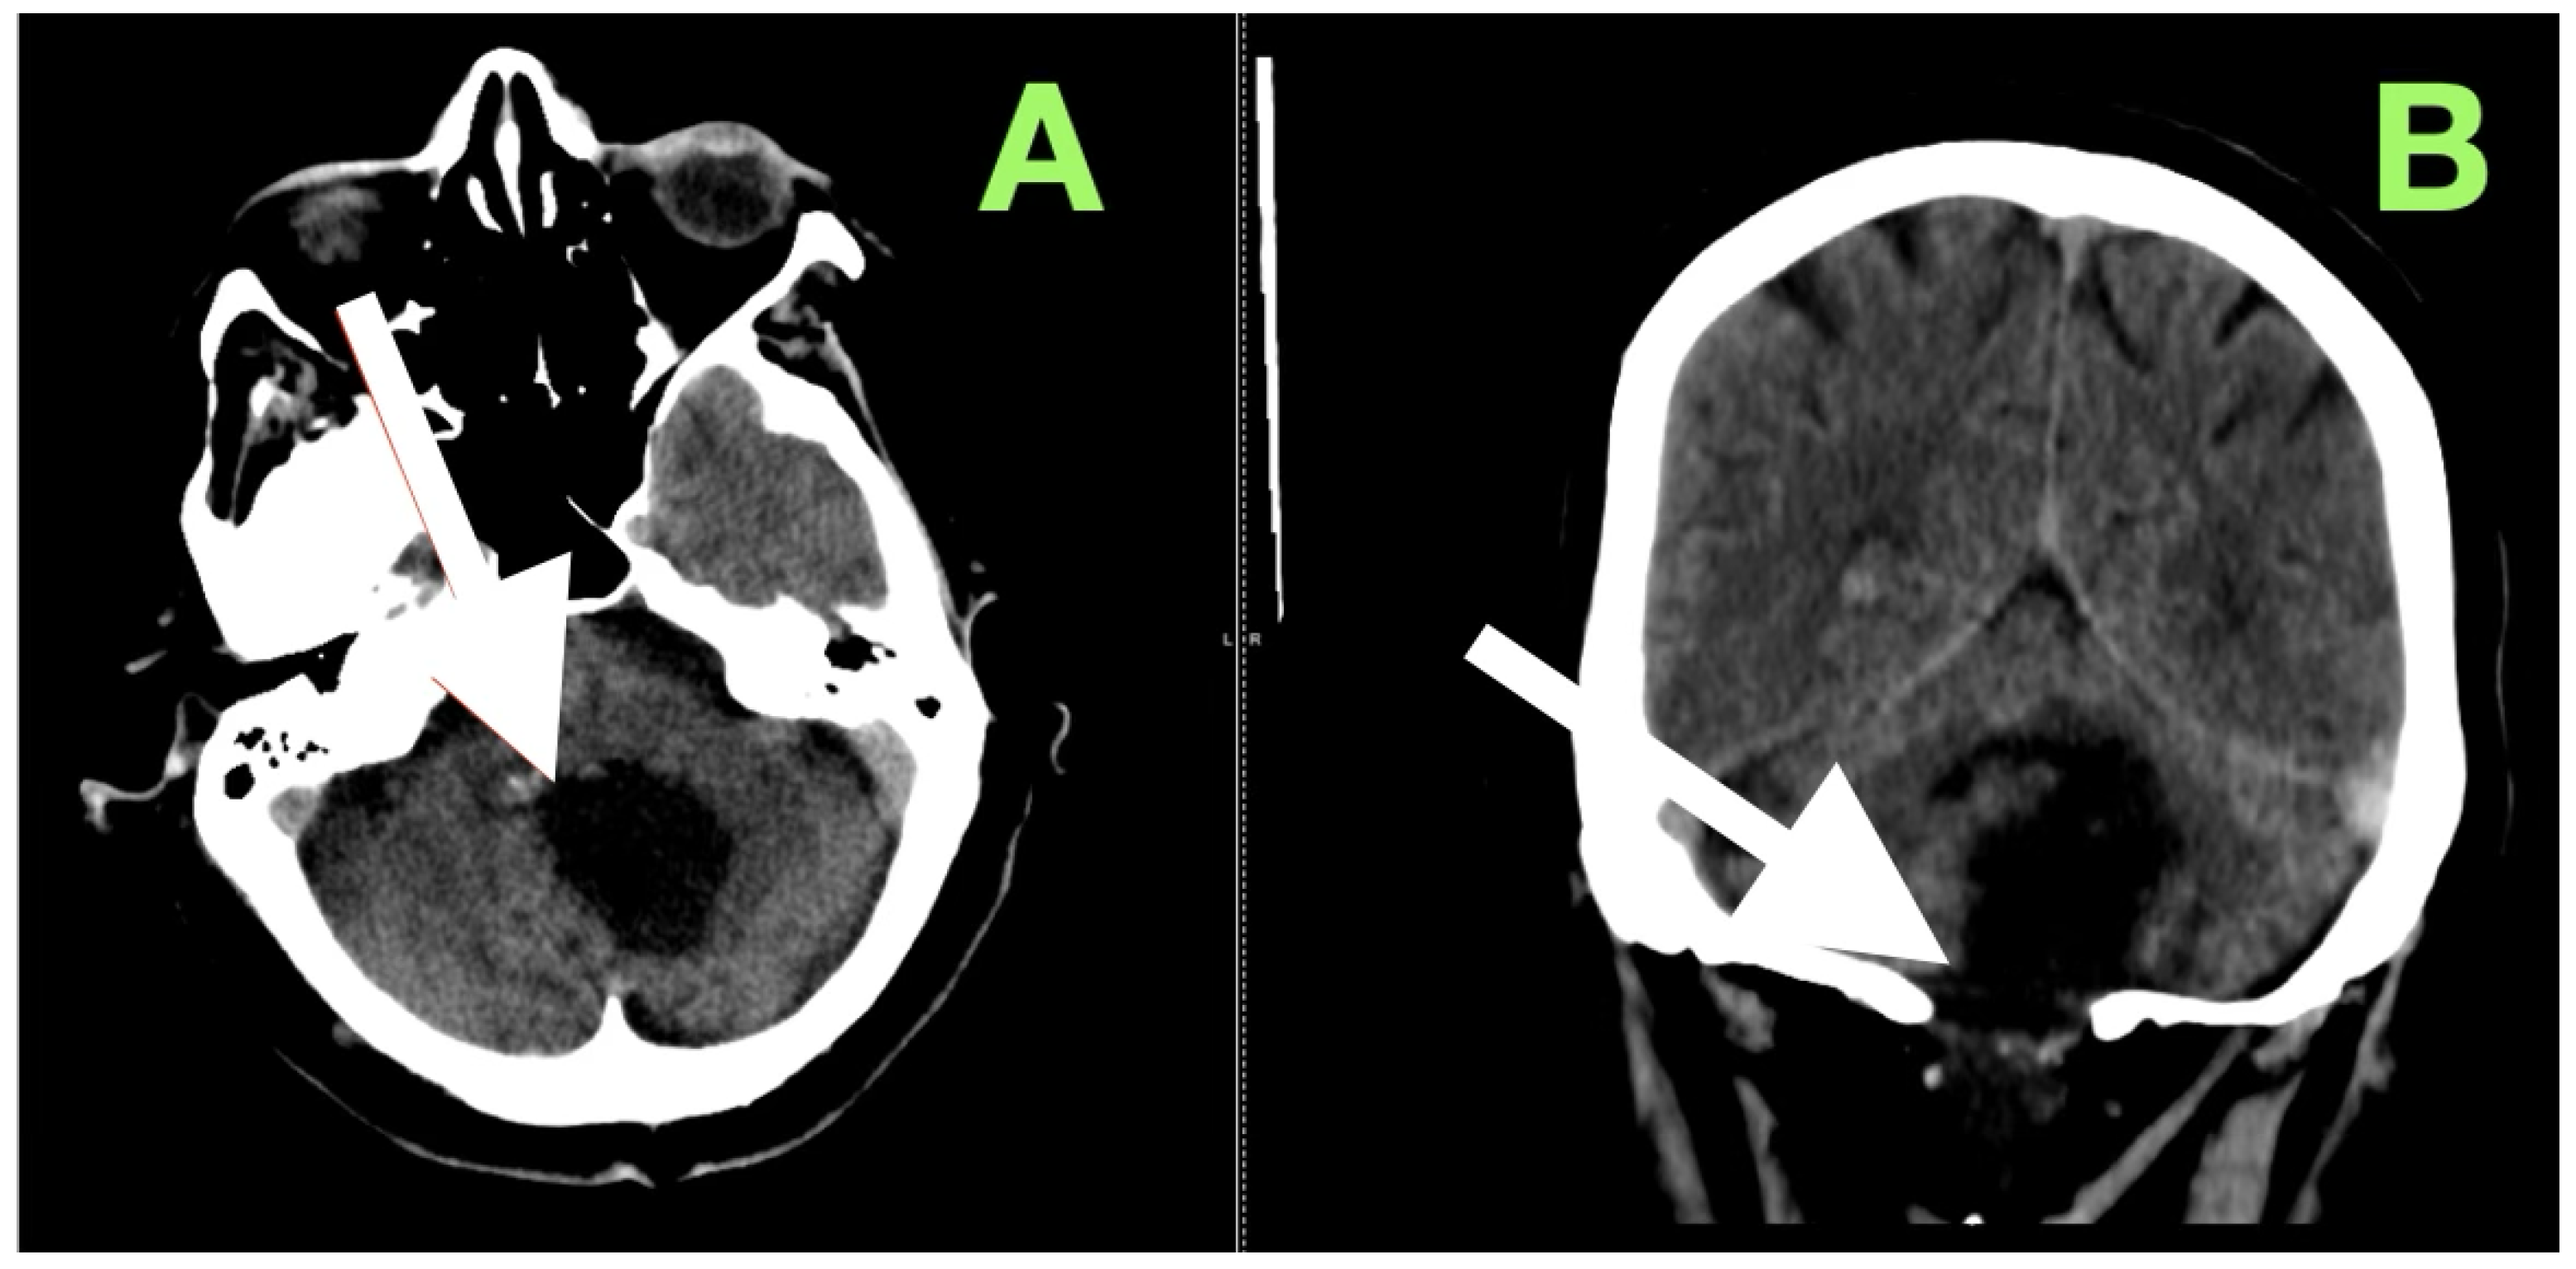

Axial T2-weighted sequences (Figure 2A,B) revealed a large, lobulated mass occupying most of the left cerebellar hemisphere, insinuating between folia and extending across the midline into the inferior vermis. The lesion was markedly hyperintense compared to cerebellar parenchyma, with internal heterogeneity suggesting layered keratinaceous content. The inferior pole of the mass descended into the cisterna magna, and its medial aspect encroached on the fourth ventricle, partially effacing it and displacing its floor anteriorly over the dorsal medulla. This displacement explained the patient’s severe truncal instability, as vermian compression interrupts integration of proprioceptive and vestibular input, and also her left-sided appendicular ataxia, arising from disruption of cerebellar hemispheric coordination pathways projecting through the dentate nucleus and superior cerebellar peduncle.

Susceptibility-weighted imaging (Figure 2C) showed tiny punctate hypointense lesions foci within lesions, suggestive of microcalcifications or hemosiderin secondary to chronic contact with the tentorium, vasculature, and pia, all indicating a long-standing, slowly growing mass. Post-contrast T1-weighted imaging (Figure 2D) displayed no enhancement, considering both lesions were different from a meningioma, hemangioblastoma, or metastasis. Coronal T2-weighted sequences (Figure 2E) demonstrated inferior and lateral extension to the foramina of Luschka, stenosing the lateral recesses of the fourth ventricle and displacing the cerebellar peduncles, most notably left. This accounted for the gaze-evoked nystagmus and pursuit deficits, considering vestibulocerebellar input and flocculonodular output. Cerebellomedullary junctional contact was responsible for the subtle bulbar discoordination secondary to pressure to the dorsal medulla near the nucleus ambiguus. Sagittal FLAIR (Figure 2F) showed an anteriorly displaced brainstem; however, the dorsal medulla was compressed against the wall of the fourth ventricle, with the pontomedullary junction displaced anteriorly. The prepontine cistern was partly effaced, and the basal cisterns were narrowed but still patent; however, inferior edema was enough for acute obstructive hydrocephalus.

Overall, the clinical–imaging cumulative data provided support for the diagnosis of an extra-axial, slow-growing epidermoid cyst, with lobulated margins, displacing the subarachnoid space, non-enhancing, and displacing chronic vessels. The MRI-clinical correlation was telling—compression via the vermis for truncal ataxia, hemispheres for dysmetria and dysdiadochokinesia, peduncles for pursuing instability, and medulla for bulbar signs. Severe compression of the fourth ventricle and effacement of the cisterns defined surgical urgency and targets that day.

Figure 2. Preoperative magnetic resonance imaging of the posterior fossa. (A,B) Axial T2-weighted images reveal a large lobulated hyperintense lesion occupying the left cerebellar hemisphere, extending medially into the vermis and inferiorly into the cisterna magna, with partial effacement and anterior displacement of the fourth ventricle. The lesion insinuates between cerebellar folia without a discrete capsule, a feature characteristic of epidermoid tumors. (C) Susceptibility-weighted imaging shows punctate hypointense foci within the lesion, likely representing calcific or hemosiderin deposits from chronic contact with adjacent neurovascular structures. (D) Axial post-contrast T1-weighted image demonstrates absence of enhancement, distinguishing the lesion from hypervascular posterior fossa neoplasms. (E) Coronal T2-weighted image depicts inferior extension toward the foramen of Luschka and compression of the cerebellar peduncles, explaining the patient’s gait instability, gaze-evoked nystagmus, and dysdiadochokinesia. (F) Sagittal FLAIR sequence confirms anterior displacement and flattening of the dorsal medulla with partial effacement of the prepontine cistern, correlating with the subtle bulbar incoordination observed on examination.